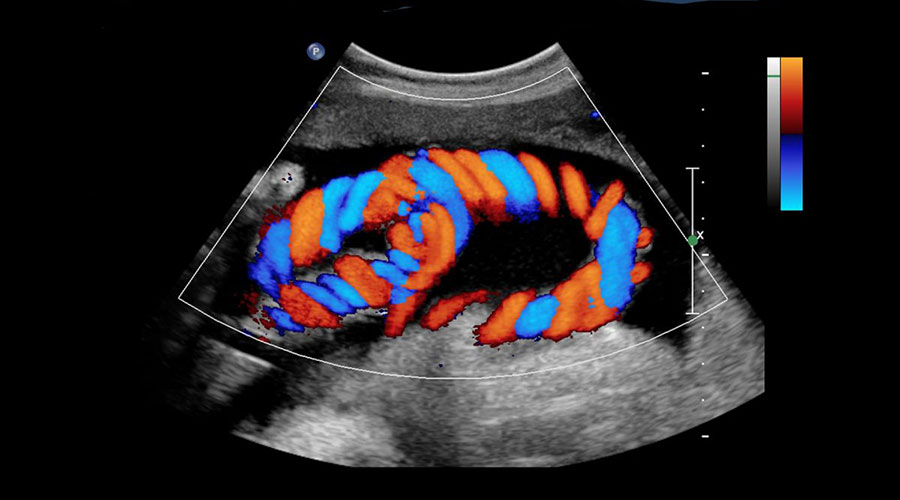

Ultrason görüntüleme tekniklerinden biri olan renkli doppler, damarlardaki kan akışını tespit etmekte ve yüksek frekanslı ses dalgaları kullanılarak vücut içinde organların görüntülenmesinde kullanılır. Önce prob aracılığı ile ses dalgaları gönderilir. Aynı şekilde geri dönen ses dalgaları, prob tarafından toplanıp elektrik enerjisine dönüştürülür. Bilgisayar aracılığı ile de görüntü haline getirilir. Vücudun birçok bölgesinin incelenmesinde kullanılır. Başlıca kullanım alanları; karın içi organlar, tiroid bezi, meme gibi yüzeyselorganlar, gebelik takibi, kalp, atar-toplar damarlar olarak özetlenebilir.

Merkezimizde GE (Logic 9) ve Siemens (Antares, Sequia) firmalarının 2003 - 2005 yılları arasında geliştirdikleri teknolojiye sahip ultrasonografi cihazları kullanılmakta ve devamlı up-grade'leri yapılmaktadır. Önceleri görülmeyen erken evre bir çok hastalık teşhis ve tedavi edilebilmektedir. Yüksek çözünürlüğü sayesinde US eşliğinde biopsiyi kolaylaştırarak tedaviyi yönlendirmektedir.